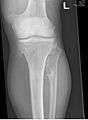

Hereditary multiple exostoses (HME or MHE), also known as diaphyseal aclasis, is a rare medical condition in which multiple bony spurs or lumps (also known as exostoses, or osteochondromas) develop on the bones of a child. HME is synonymous with multiple hereditary exostoses and multiple osteochondromatosis, which is the preferred term used by the World Health Organization.

It is characterized by the growth of cartilage-capped benign bone tumours around areas of active bone growth, particularly the metaphysis of the long bones. Typically five or six exostoses are found in upper and lower limbs. Most common locations are:[1]

HME can lead to the shortening and bowing of bones; affected individuals often have a short stature. Depending on their location the exostoses can cause the following problems: pain or numbness from nerve compression, vascular compromise, inequality of limb length, irritation of tendon and muscle, Madelung's deformity[2] as well as a limited range of motion at the joints upon which they encroach. A person with HME has an increased risk of developing a rare form of bone cancer called chondrosarcoma as an adult.[2] Problems may be had in later life and these could include weak bones and nerve damage.[3][4][5] The reported rate of transformation ranges from as low as 0.57%[6] to as high as 8.3% of people with HME.[7]

Diagnosis is mostly clinical and radiological. Technetium skeletal scintigrams are occasionally used to determine number of exostoses.[17]